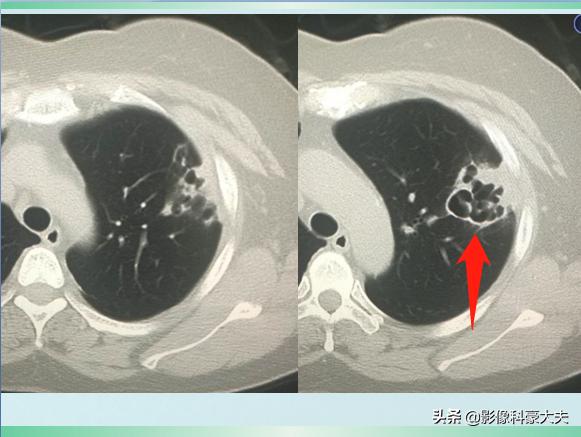

这是一位62岁的退休教师,因为淋雨受凉后出现高热、胸痛、咳嗽症状,自服感冒药无效,在家里拖了3天才过来,已经是重症肺炎,肺组织广泛坏死了,后来没有抢救回来……

这类重症肺炎的进展常常很凶猛,比癌症还厉害,早期积极治疗很关键!